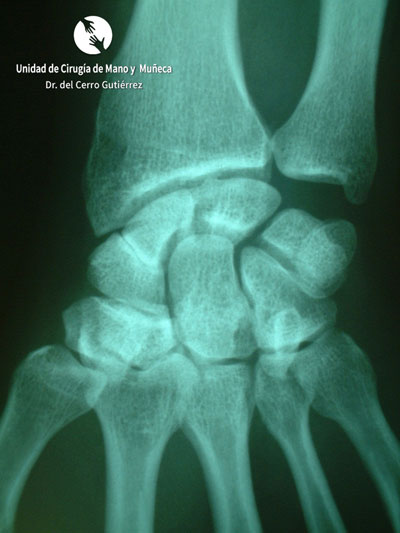

Fractura del Escafoides. Fractura del Polo Proximal

Fractura del Polo Proximal

Fractura del polo proxima del escafoides de la mano

Fractura del escafoides. Polo Proximal

Fractura de escafoides de la mano. Polo Proximal